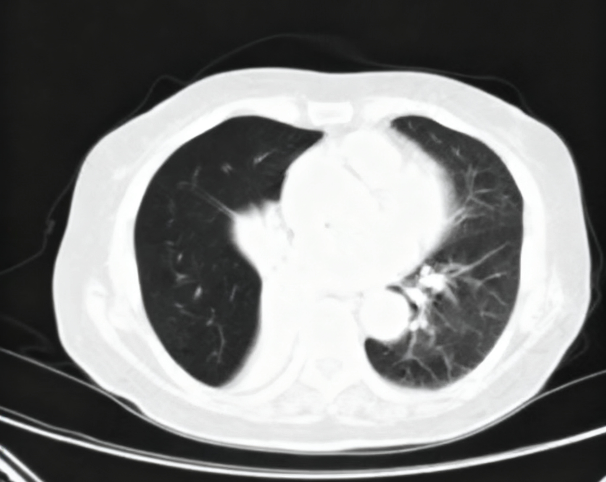

夏奶奶近两年来一直被间断的胸闷、气短、咳嗽、咳痰困扰。半月前,她的病情急剧加重,出现了痰中带血的症状,家人紧急送至东院区。呼吸与危重症医学科阎杰副主任医师接诊后,立即为夏奶奶进行胸部增强CT检查。结果提示“右肺门增大,右肺主支气管内结节状软组织密度灶,右肺下叶不张”,高度怀疑恶性肿瘤。

患者CT检查